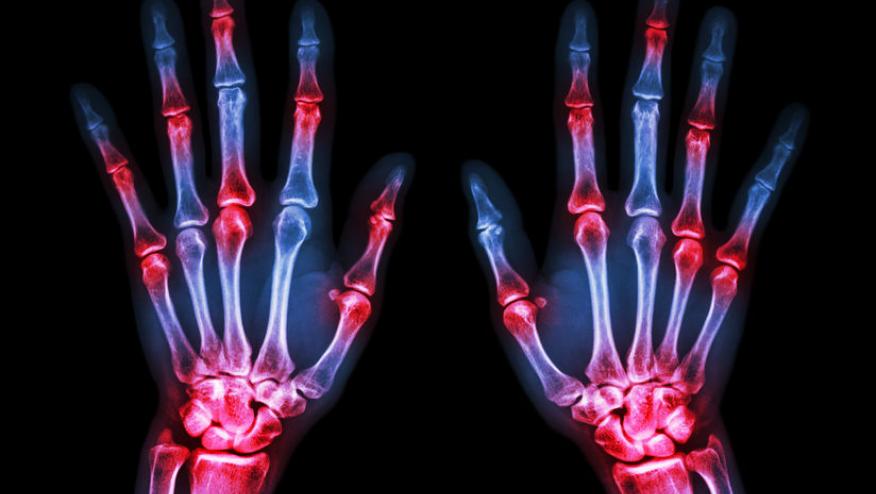

In the last 2 years, there has been more caution and vigilance with the use of JAK inhibitors in the treatment of rheumatoid arthritis (RA) due to the risk of cardiovascular (CV) events. These CV events include major adverse cardiac events (MACE) and venous thromboembolic events (VTE). The publication of the ORAL surveillance study (1), a post-approval safety study conducted in RA patients aged ≥50 years with ≥1 CV risk factor, has resulted in increased caution and greater emphasis on assessment of MACE and VTE risks in patients starting JAK inhibitors.